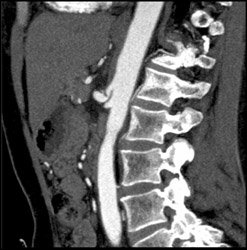

Median Arcuate Ligament Syndrome